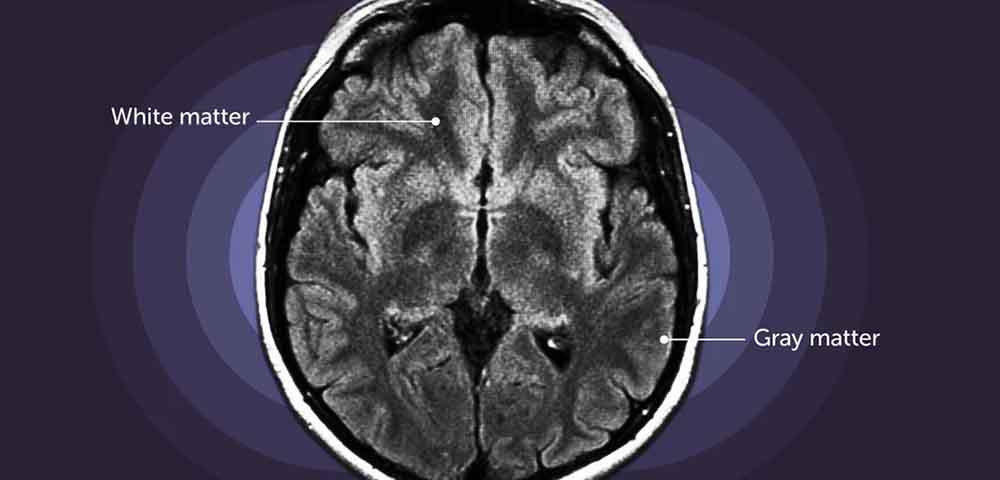

According to a recent study, the grey matter volume in pregnant women decreases by roughly five per cent and a partial recovery occurs in the postpartum phase. The brain’s outermost layer and interior are made up of grey matter, which aids in information processing and interpretation, enabling thinking, learning, and memory.

In 94 per cent of the brain, grey matter was found to have changed. This shift was most noticeable in the default mode network, which is known to support social cognition. The study was published in the journal ‘Nature Communications’. Researchers discovered that a stronger mother-infant relationship was associated with a higher recovery of grey matter.

The study’s authors also found out that a U-shaped trajectory in grey matter volume dips in late pregnancy and partially recovers during the postpartum period. The U-shaped trajectory in GM volume impacted several areas throughout the brain’s cortex, covering 94 per cent of its surface. Changes in higher-order cognitive networks, including the frontoparietal and default modes, were especially noticeable. Additionally, the study demonstrated that the alterations in the brain associated with pregnancy were linked to variations in the levels of two estrogens, ‘estriol-3-sulfate’ and ‘estrone-sulfate.’